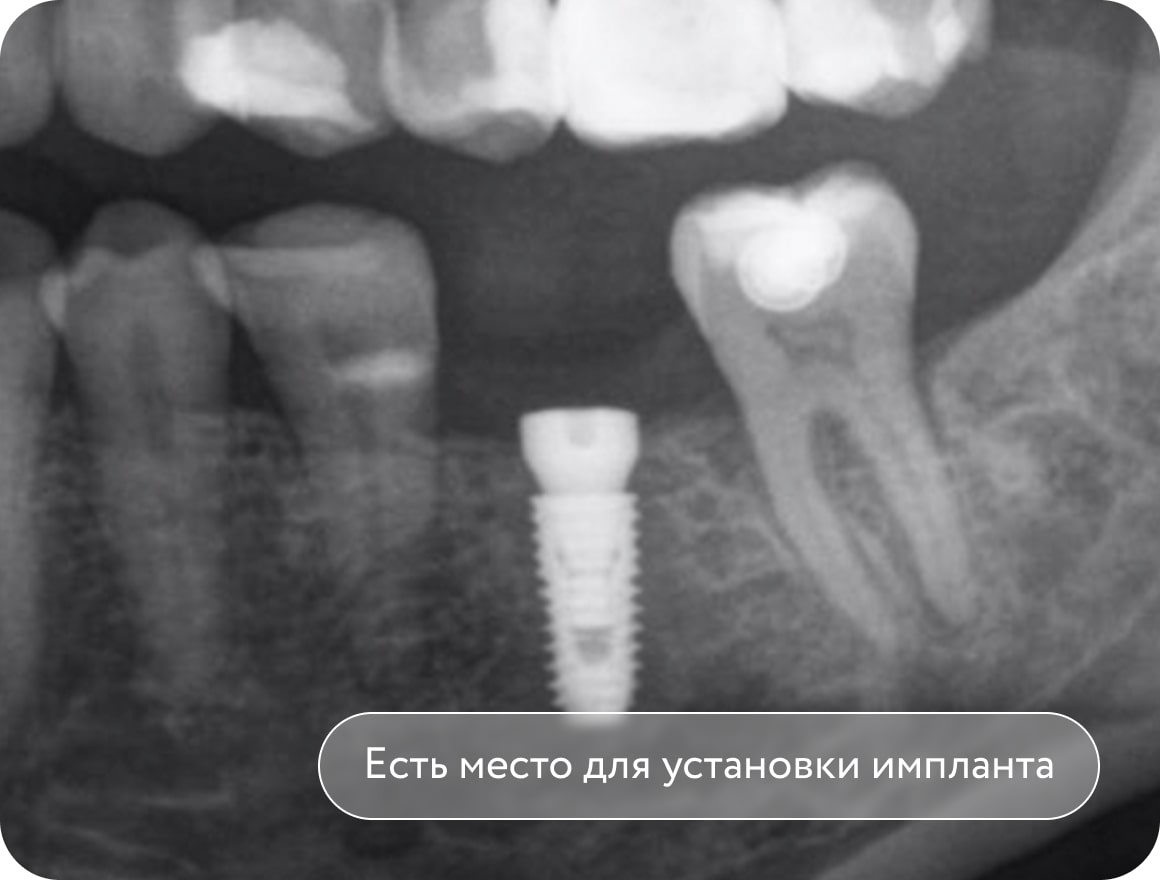

Установка мини-винта, вытягивание 2 моляра с помощью резинок. Создание места для имплантации в области 1 моляра. Срок лечения 3 месяца